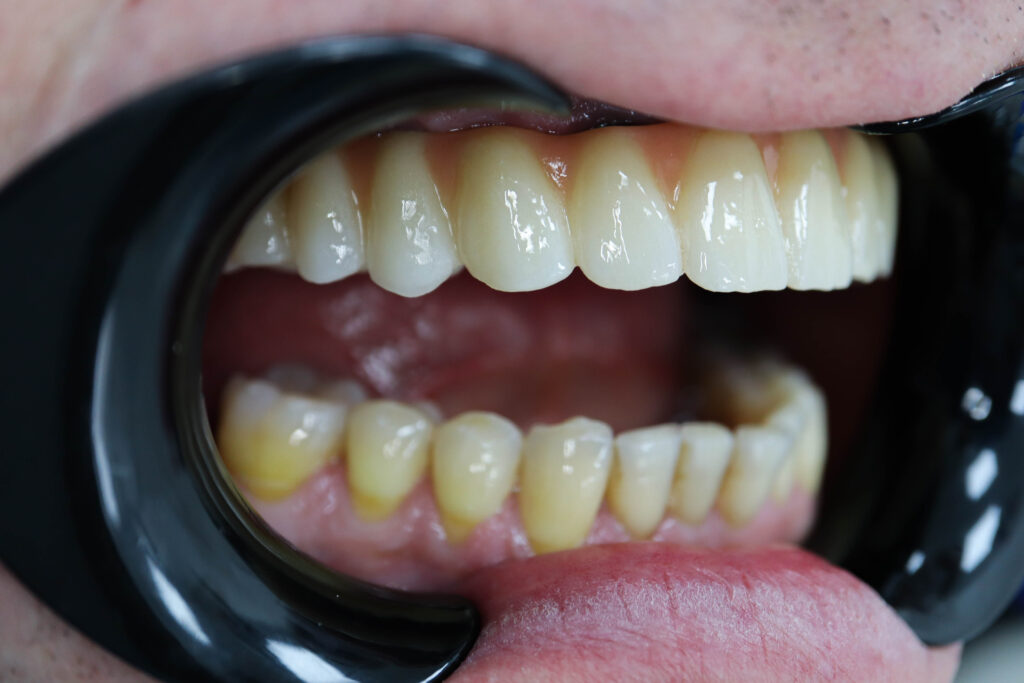

Пациент продолжает лечение спустя 3 месяца после имплантации и установки временного металлоакрилового протеза с опорой на 6-ти дентальных имплантантах Megagen Anyone.

Лечение начато с выбора материала для будущей конструкции (диоксид циркония на титановой балке) и цвета.

Был установлен временный протез из PMMA, максимально воссоздающий форму и цвет (А3) будущей конструкции.

Спустя 25 дней был зафиксирован протез с опопрой на дентальные имплантаты из диоксида циркония с армированием из титана.